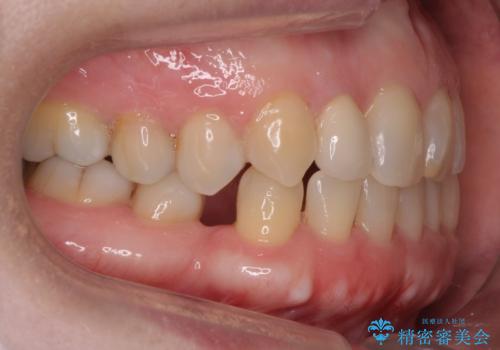

- 右上の2番目の前歯がとがった形をしていたため、セラミックで形を整えています。

短くてとがった歯の形が反対側と同じ形となり、左右対称となり、ずいぶん自然な印象になりました。

- 右上2 15.4万円(内訳 ジルコニアクラウンスペシャル 13万円、仮歯 1万円)費用は治療当時の料金となります

下の前歯とのかみ合わせが切端咬合だったため、前歯の部分矯正も併せて行っています。(費用別途)